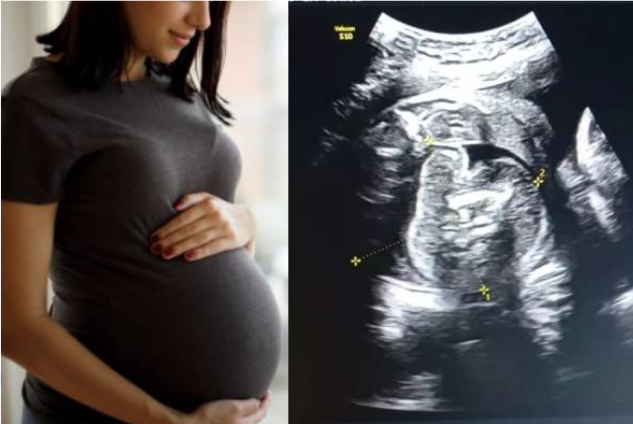

கர்ப்பிணியின் வயிற்றில் உள்ள குழந்தைக்குள் வளரும் கரு – மிரண்ட மருத்துவர்கள்!

பெண்ணின் வயிற்றில் உள்ள குழந்தைக்குள் கரு வளரும் சம்பவம் ஆச்சர்யத்தை ஏற்படுத்தியுள்ளது.

மகாராஷ்டிராவில் புல்தானா மாவட்டத்தின் அரசு பெண்கள் மருத்துவமனை செயல்பட்டு வருகிறது. இங்கு 9 மாத கர்ப்பிணி சிகிச்சை பெற்று வந்துள்ளார்.

அவருக்கு சோனோகிராபி செய்தபோது அவரின் கருவில் முழு வளர்ச்சியடையாத கரு வளர்வது கண்டறியப்பட்டுள்ளது. இதுகுறித்து அந்த மருத்துவமனையின் மகப்பேறு மருத்துவர் பிரசாத் அகர்வால் கூறுகையில்,

இதுவரை உலகில் வெறும் 200 பேருக்கு மட்டுமே இதுபோல நிகழ்ந்துள்ளது. 5 லட்சத்தில் ஒருவருக்கு மட்டுமே நடக்கக்கூடிய நிகழ்வு. இந்த நிலைக்கான சரியான காரணம் எதுவும் கூறப்படவில்லை. ஆனால், இது ஒரே மாதிரியான இரட்டையர்களின் வளர்ச்சியின் போது நிகழும் ஒழுங்கின்மையின் விளைவு என கருதப்படுகிறது.